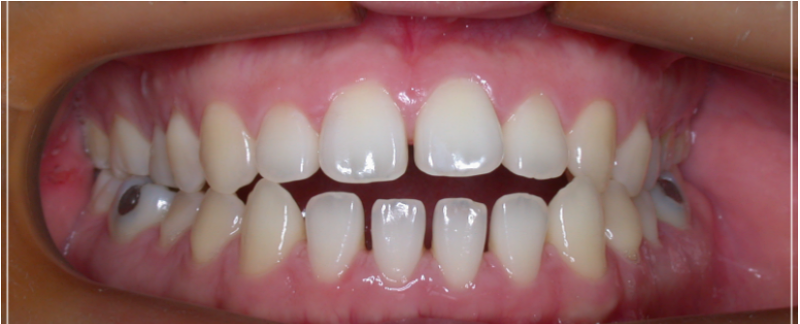

이 처럼 입을 다물어도 어금니만

맞물린 채 앞니가 맞물리지 않는 증상을

개방교합이라고 부르는데요.

보통 우리가 입을 다물 때

상,하악의 치아의 모든 면이 전체적으로

맞닿는 것이 정상적인 형태이지만,

개방교합은 입을 다물때 안쪽

어금니만 맞닿고 앞니 쪽은 닿지 않아

입술이 붕 떠 있는 상태를 말했어요.

이처럼 앞니가맞물리지 않고

붕 떠있는 증상이 오랜기간 지속되면

점차 얼굴 안면 골격의 부정적인

변화를 발생시키기도 하기 때문에